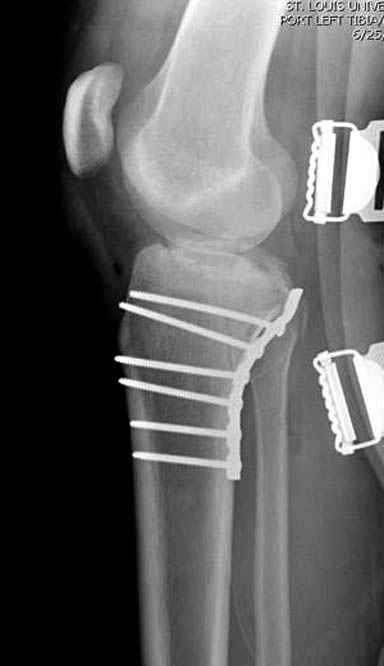

Пациенту сделали КТ - ухитрились сделать на шине Белера (не давал положить прямую ногу) - срезали передний отдел. Планируется на пятницу (24.12) на операцию - синтез длинной мыщелковой LCP-пластиной Synthes :). Отек ближе к слову умеренный (окружность голени +4 см по сравнению со здоровой). КТ и снимок на вытяжении прилагаются.

Уважаемые коллеги! В прошлую пятницу больной прооперирован - как и планировалось мыщелковая LCP от ChM. Малоинвазивно не получилось - один большой доступ :(. (но с минимальным скелетированием б/б кости). Наружный мыщелок собрали, но по контролю видно, что задне-медиальный отдел метаэпифиза смещен. Фиксировать не стали (?). 4-е сутки после операции - по м/тканям без проблем. Дополнительная иммобилизация синтетическим тутором.

P. S. перелом диафиза на контроле не совсем захвачен, но проблем там нет. Приношу извинения за низкое качество Р-грамм - выполнены на сканере (фотоаппарат не работает :)) .

Трудно поверить, что разрекламированная Ортопедическая школа Восточной Украины позволяет такие странные снимки? На прямом снимке сохранен общий контур плато, но не известна судьба импрессии суставной поверхности. На полубоковой?, оставлен без репозиции задне-медиальный отдел, и навряд ли после такой фиксации можно удовлетвориться результатом.

Такая ситуация характерна для многих, когда принимается ошибочное решение, т.е пытаются фиксировать одним имплантом переломы двух мыщелков. Латеральная пластина приемлема только для тех случаев, когда сохраняется интактным медиальный диафизарный кортекс и отсутствует фрагментация на верхушке медиального перелома.

Здесь как раз тот случай, когда результат зависит не только от мастерства хирурга, но и от наличия современных методов исследования. Например, КТ которая поможет рассчитать направления шурупов и установку импланта. Кроме этого, поможет определиться с доступом.

На представленных предоперационных срезах КТ огромный задне-медиальный фрагмент расположен больше кзади, чем медиально. Для планирования, кроме поперечных срезов, надо ориентироваться на корональные срезы, которые укажут топографию верхушки медиального фрагмента.